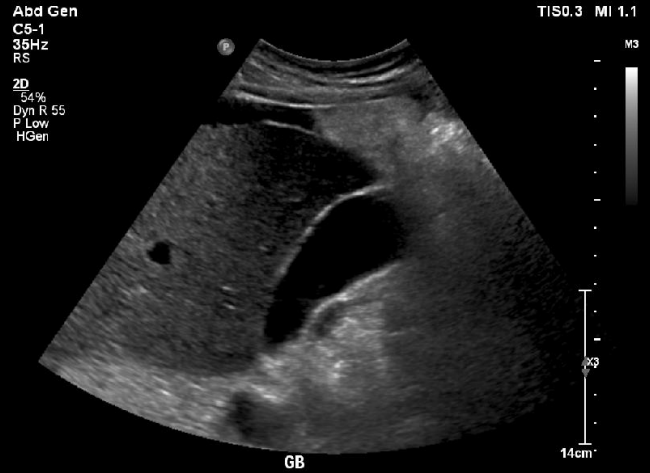

¿Qué signo ecográfico es típico de litos vesiculares?

Sombra sónica posterior (HIPERECOGENICIDADES)